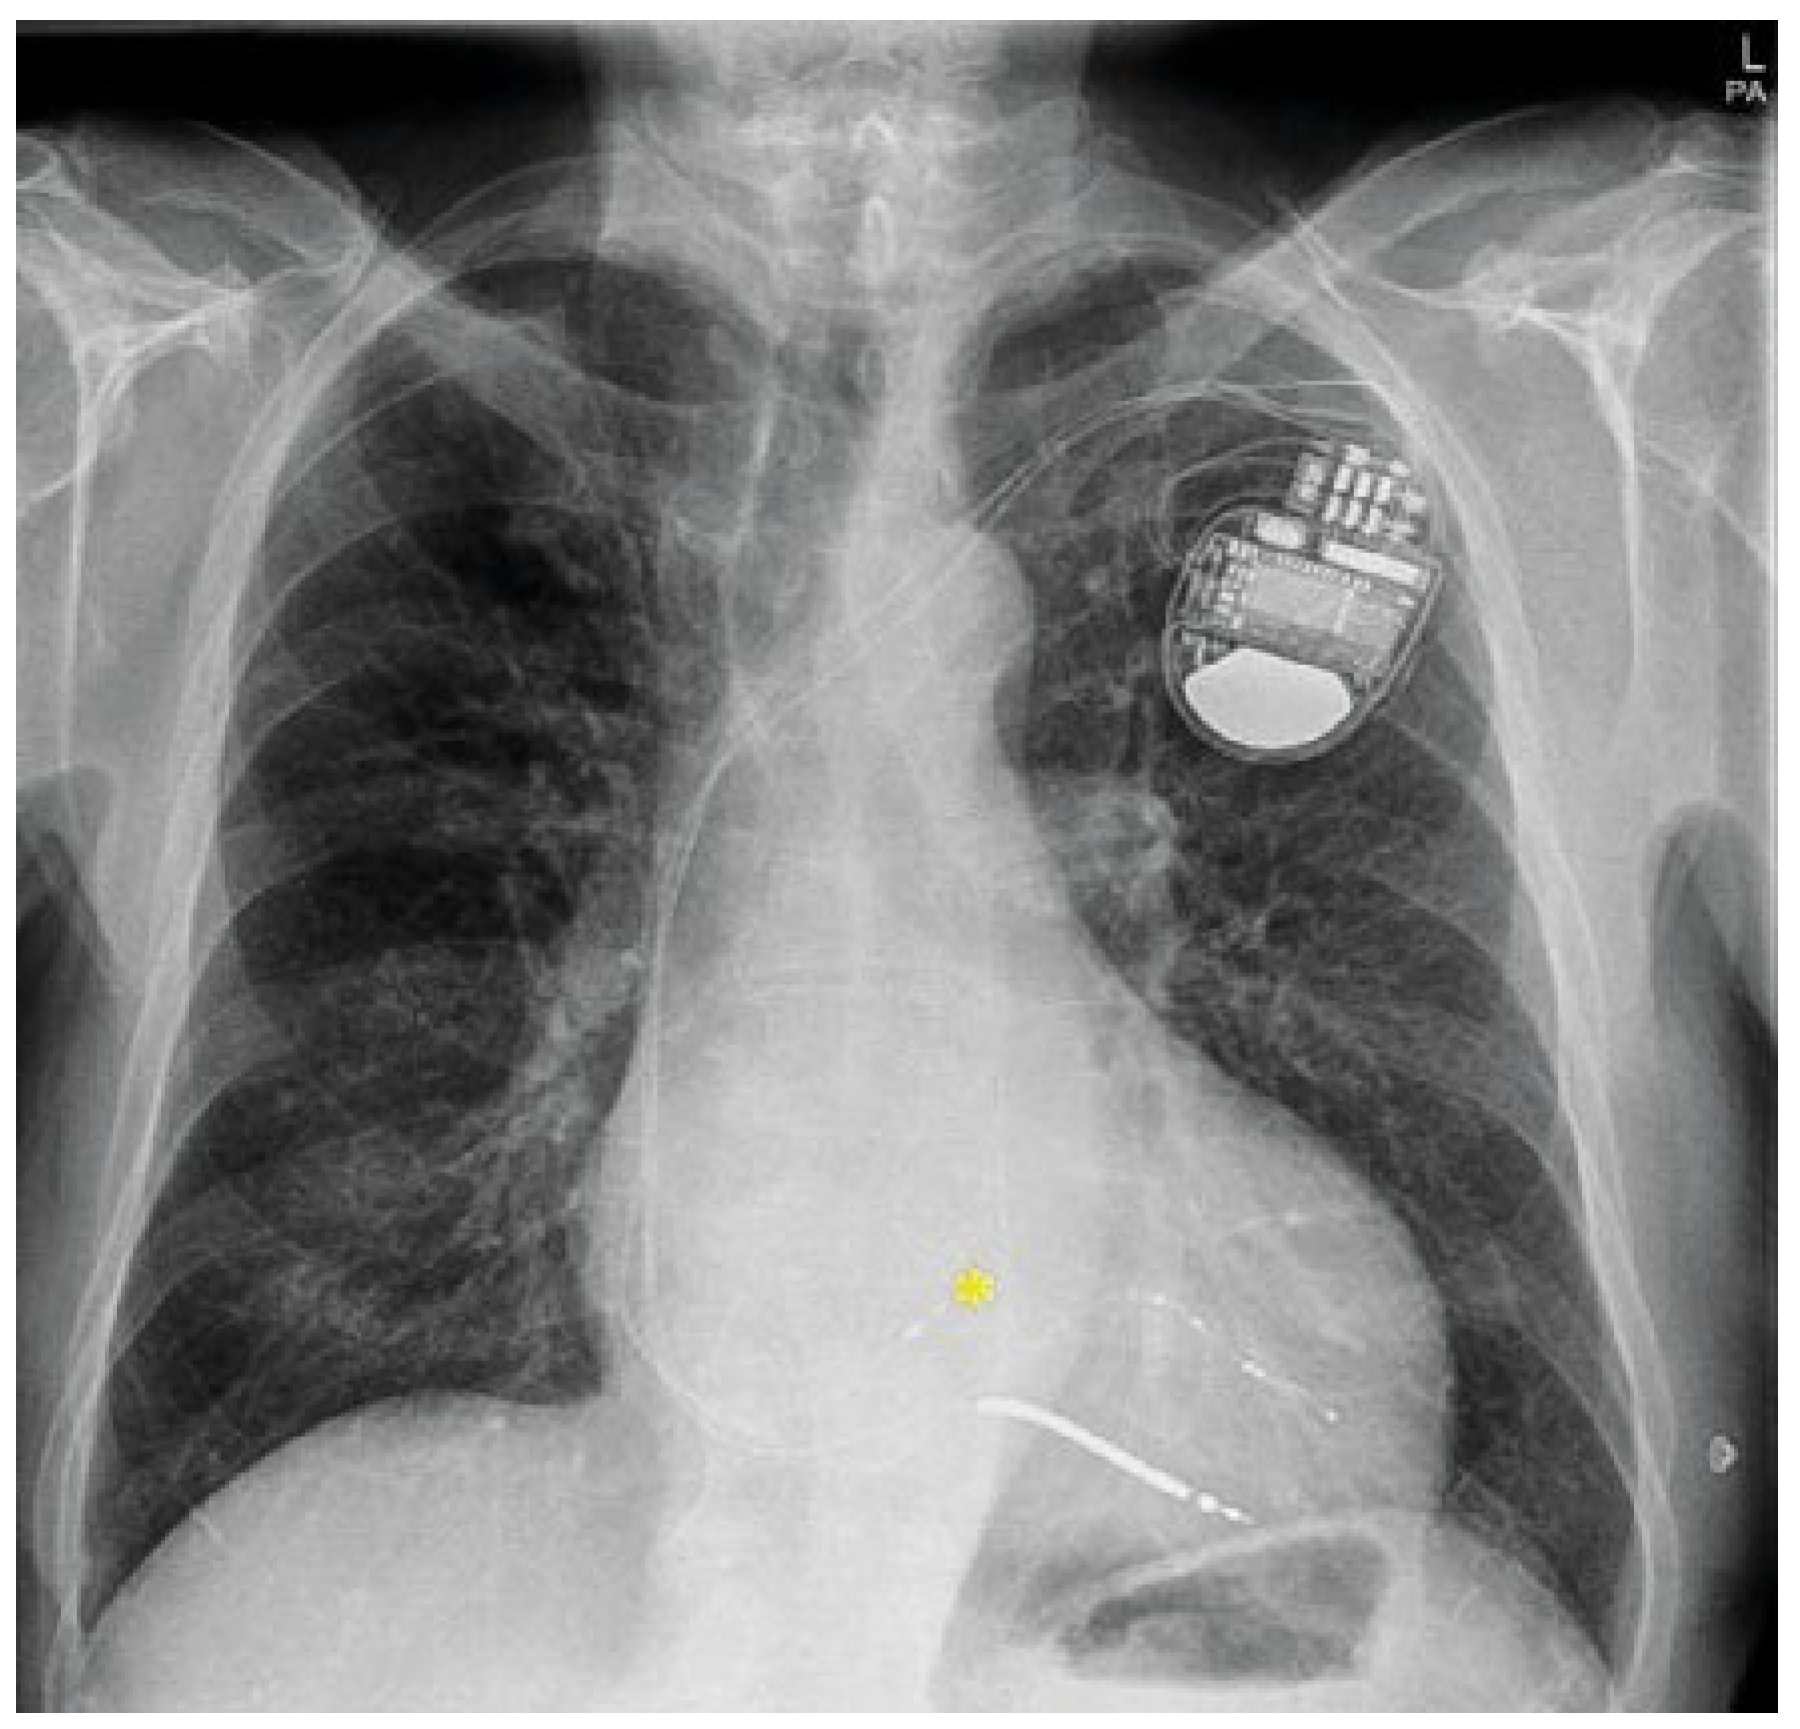

Via a left subclavian venous access, a right ventricular shock lead (Medtronic, Sprint Quattro Secure S MRI SureScan 6935M62 cm) as well as a quadripolar left ventricular lead (Medtronic, Attain Stability 88 cm) were implanted. The latter was successfully positioned in a posterolateral coronary sinus side branch (Figure 1). Intrinsic left ventricular delay (QLV) was 114 ms with a promising high QLV/QRSd ratio of 0.95. Symmetrical paced-to-sensed delays (RVp-LVs = LVp-RVs = 120 ms) indicated bidirectional homogeneous ventricular activation. However, the acute electrical result of biventricular pacing was disappointing, with a broad QRS of 156 ms (Figure 2) despite an optimised pacing configuration.

Figure 1. Chest x-ray in postero-anterior view. Ccardiac resynchronisation therapy-defibrillator device with right ventricular shock lead, quadripolar lead in a posterolateral side branch of the coronary sinus and His pacing lead (yellow asterix).